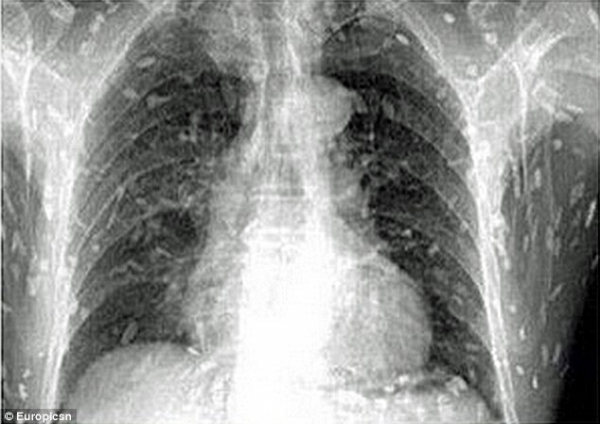

وأفاد موقع "شاينا توبيكس" الصيني أن رجلاً من مقاطعة غوانغدونغ في جنوب شرق الصين، كان يشكو من ألم في المعدة وتحسس في جلده، فذهب إلى الطبيب ليتلقى صدمة حياته إذ أثبتت الصور بالأشعة أن الديدان الشريطية تغزو مختلف أنحاء جسمه

وأشارت إلى أنه يعتقد أن الديدان انتشرت في جسم هذا الرجل، إثر تناوله من طبق محبب إلى قلبه هو طبق "ساشيمي" ملوث، الذي يعد من أفخر أنواع "السوشي"

ونقل عن أحد الأطباء قوله إن الرجل يتلقى العلاج المناسب، مشيراً إلى أن تناول طعام غير مطبوخ ملوث ببيض الديدان الشريطية قد يقود إلى حالة صحية تهدد الحياة، إذا دخلت هذه الديدان في مجرى الدم ووصلت إلى الدماغ